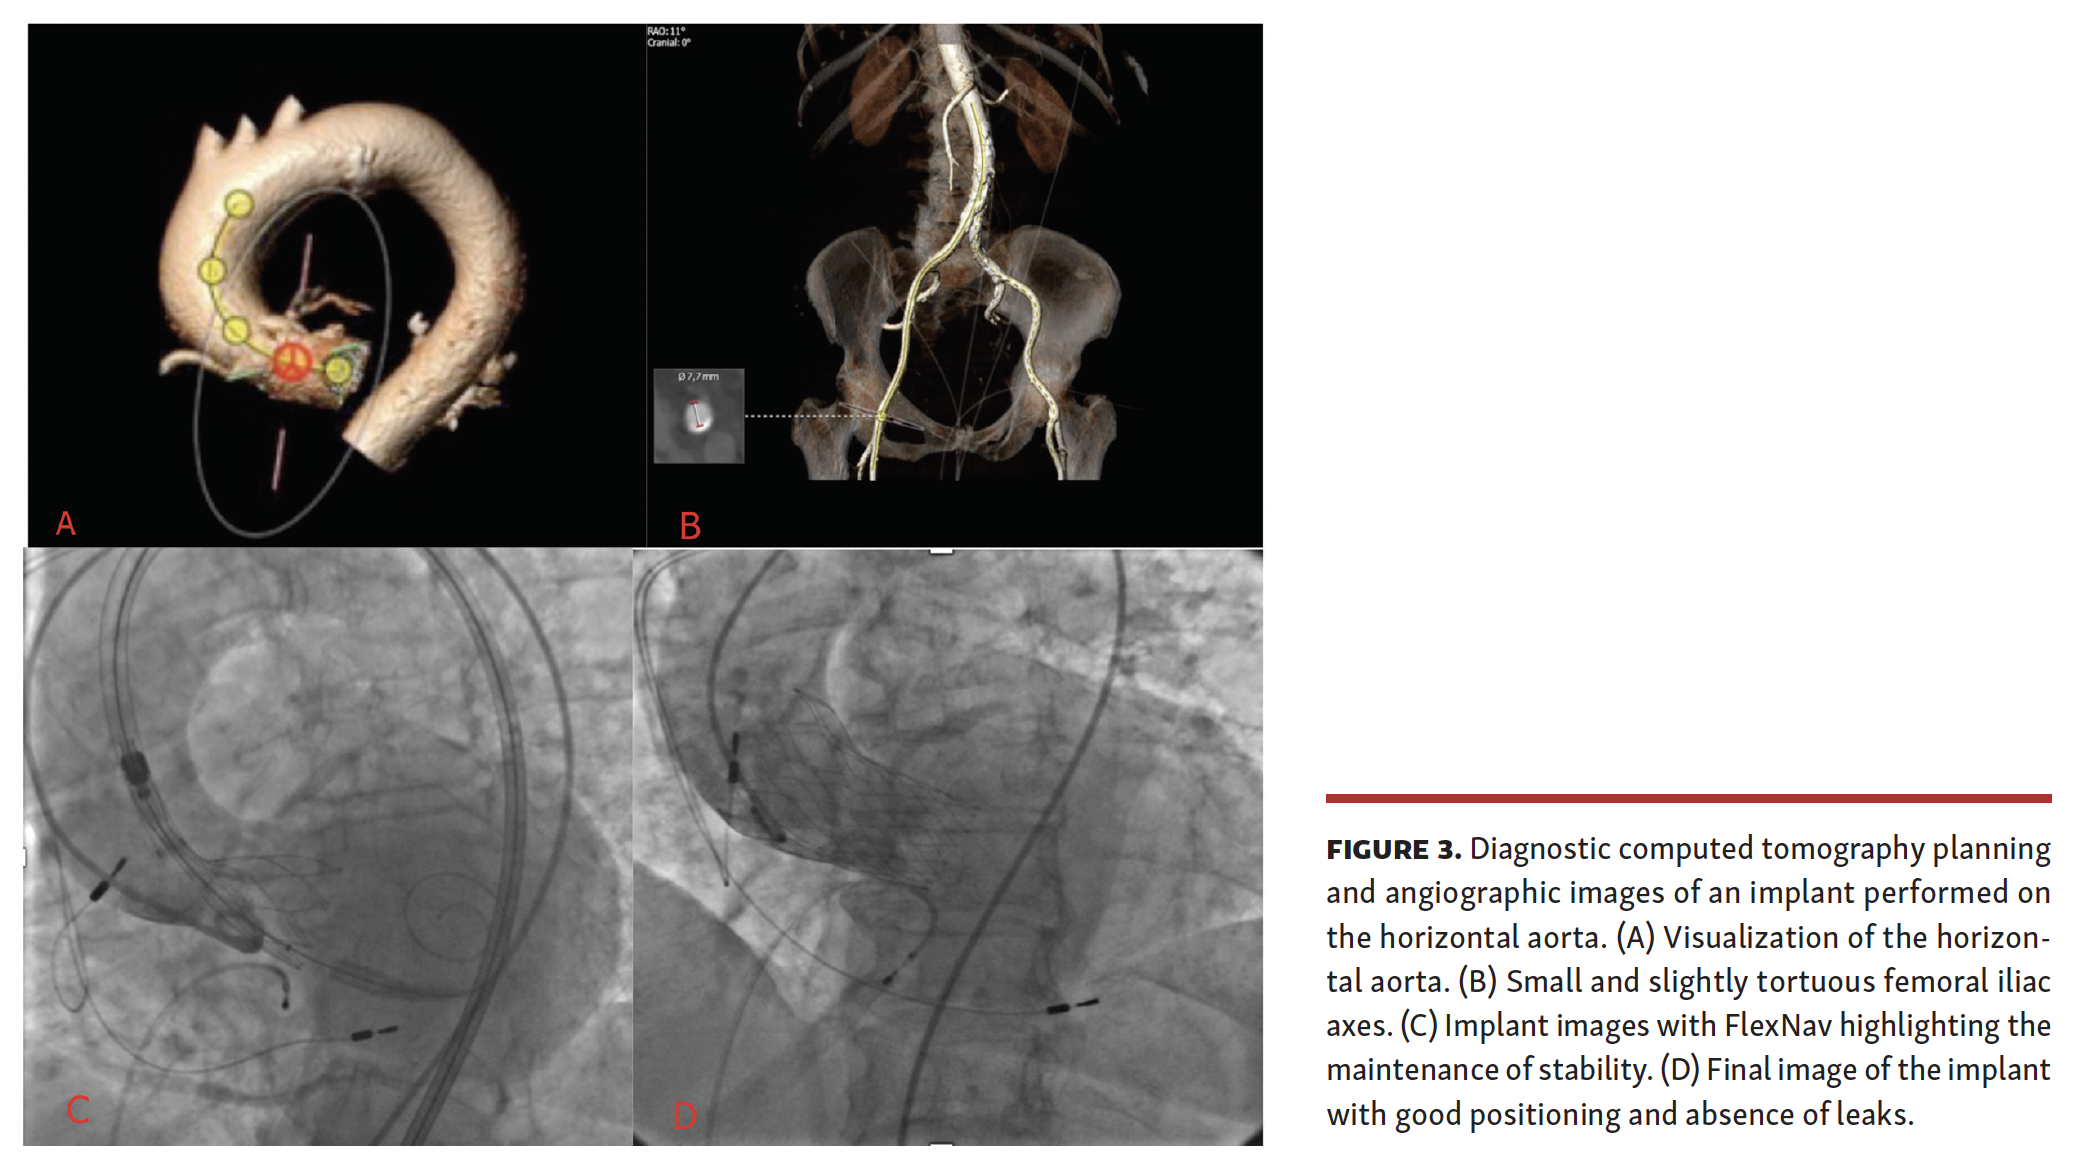

The landscape of structural heart disease is expanding momentously, with novel devices being introduced almost every month for mitral or tricuspid valve disease.16 In this setting, TAVI represents a pioneering intervention for valve disease. Despite being relatively young (at least in comparison with percutaneous coronary intervention), TAVI has already met many seminal milestones, such as toppling the role of medical therapy in patients with absolute contraindications to surgery and actively challenging SAVR in subjects at intermediate-to-high surgical risk.1,2 Despite these successes, the activation and implementation of a TAVI program remains challenging, given the multidimensional challenges faced by invasive cardiologists as well as surgeons (Figures 1-3).17 A key factor to consider is the availability of several TAVI devices, each with its own strengths, weaknesses, and subtleties. Furthermore, device improvements are often provided, which may (hopefully favorably) shift the overall risk-benefit profile of the product.18

We hereby present our clinical experience with the novel FlexNav delivery system for Portico valve implantation in patients undergoing TAVI at our institution in early 2020.10,11 This delivery system is characterized by small size, hydrophilic coating, and controlled release function, thus expanding the indications of TAVI with Portico, and increasing the safety and ease of the procedure. In our case series, we did not recognize any meaningful risk of suboptimal control due to a potential “slipperiness” of the overall system. Moreover, we found that the new delivery system did not intuitively influence the properties of the valve, but allowed a better, more precise delivery and enhanced the eventual procedural result. Furthermore, the new delivery system is easy to handle and offers a series of qualities useful for the operator. There is also greater stability and improved flexibility compared with the previous generation of the delivery system. Among the cases treated, 2 patients had a calcified and tortuous aortoiliac axis, such as to complicate the transition from the iliac tract to the abdominal aorta. In such patients, without the need to upgrade guidewire stiffness, it was possible to overcome the challenging anatomy through a counter-clockwise rotation, thanks to the hydrophilicity of the device. Similarly, in cases treated with transaxillary access, the device behaved favorably by gaining access without the introducer, and by maintaining stability during valve implantation.